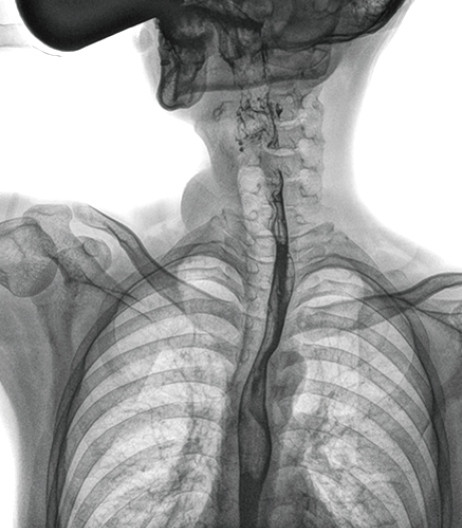

食管造影是食管病變的基本檢查方法,可以發現食管癌的特征性改變——食管粘膜的中斷和破壞,病人常感覺吞咽障礙,此特征在臨床中最常見,也是早期食管癌的典型表現。一般伴隨的特征有管壁充盈缺損、龕影、軟組織塊影、食管腔狹窄等;在透視下還可看到食管壁僵硬、蠕動緩慢等。

動態DR能夠實現大幅面透視,瞬時高清點片等。在食管造影檢查中,由于吞咽鋇劑后,造影劑流速非常快,在一個大幅面上方便觀察食管的病變。瞬時點片,可以實時捕捉到病變部位的影像,從而可以快速做出診斷。普利德多功能動態DR擁有17×17英寸超大視野,一次曝光即可顯示整個食管,更方便觀察食管的病變,確定病變的范圍,對診斷和治療有重要參考價值。

動態DR可以動態觀察管壁蠕動是否僵硬,以鑒別良、惡性狹窄,不但在透視過程中,可實時高清點片,實現毫秒級動靜態圖像切換,快速捕捉病變部位的影像,成像清晰而迅速,盡可能減少食管功能性障礙患者因吞咽困難而忍受痛苦的時間,同時提高醫生做出正確診斷的效率,還能實時保存視頻影像,反復觀察、分析,明確病變范圍,對手術有重要的指導意義。

與過去的數字胃腸機比較,動態DR圖像分辨率高,對食管的全景觀察,局部粘膜破壞、中斷,管腔狹窄以及病灶范圍的顯示清晰度明顯更優。

上消化道造影高清圖像

由此不難看出,動態DR在食管造影的臨床應用上,相比于其他檢查手段,成像清晰、應用便捷,而且能夠充分顯示食管的局部和整體結構形態,并以此揭示相關形態和功能性改變,更有利于助力實現精準診斷。